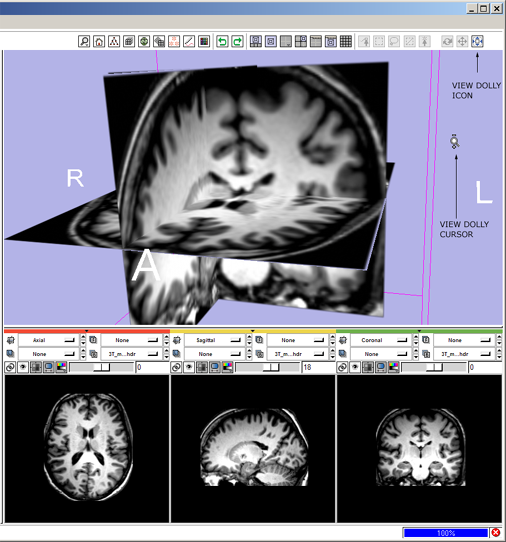

2(novice) dolly: click the view dolly mouse-mode icon ![]()

- --> mouse-dolly icon hightlights and all others deselect, cursor changes to i ndicate mouse-dolly mode.

- then left-Click and drag in the 3D Viewer to dolly the camera in and out.

2(expert) dolly: shift+left-Click and drag in the 3D Viewer

- --> mouse-dolly icon

highlights and all others deselect; cursor changes to indicate mouse-dolly mode; view zooms.

highlights and all others deselect; cursor changes to indicate mouse-dolly mode; view zooms.